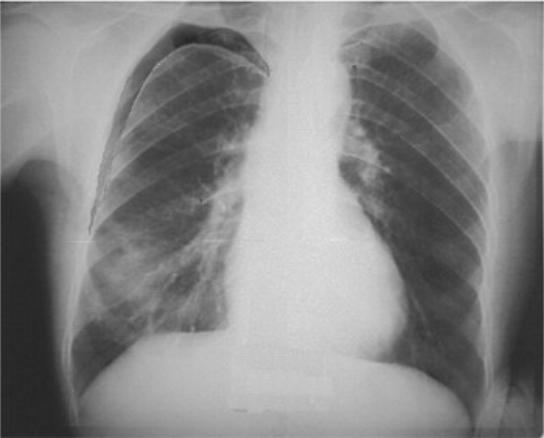

Рентгенодиагностика бронхопневмонии: Советы и примеры

Раздел: Альбом открытий